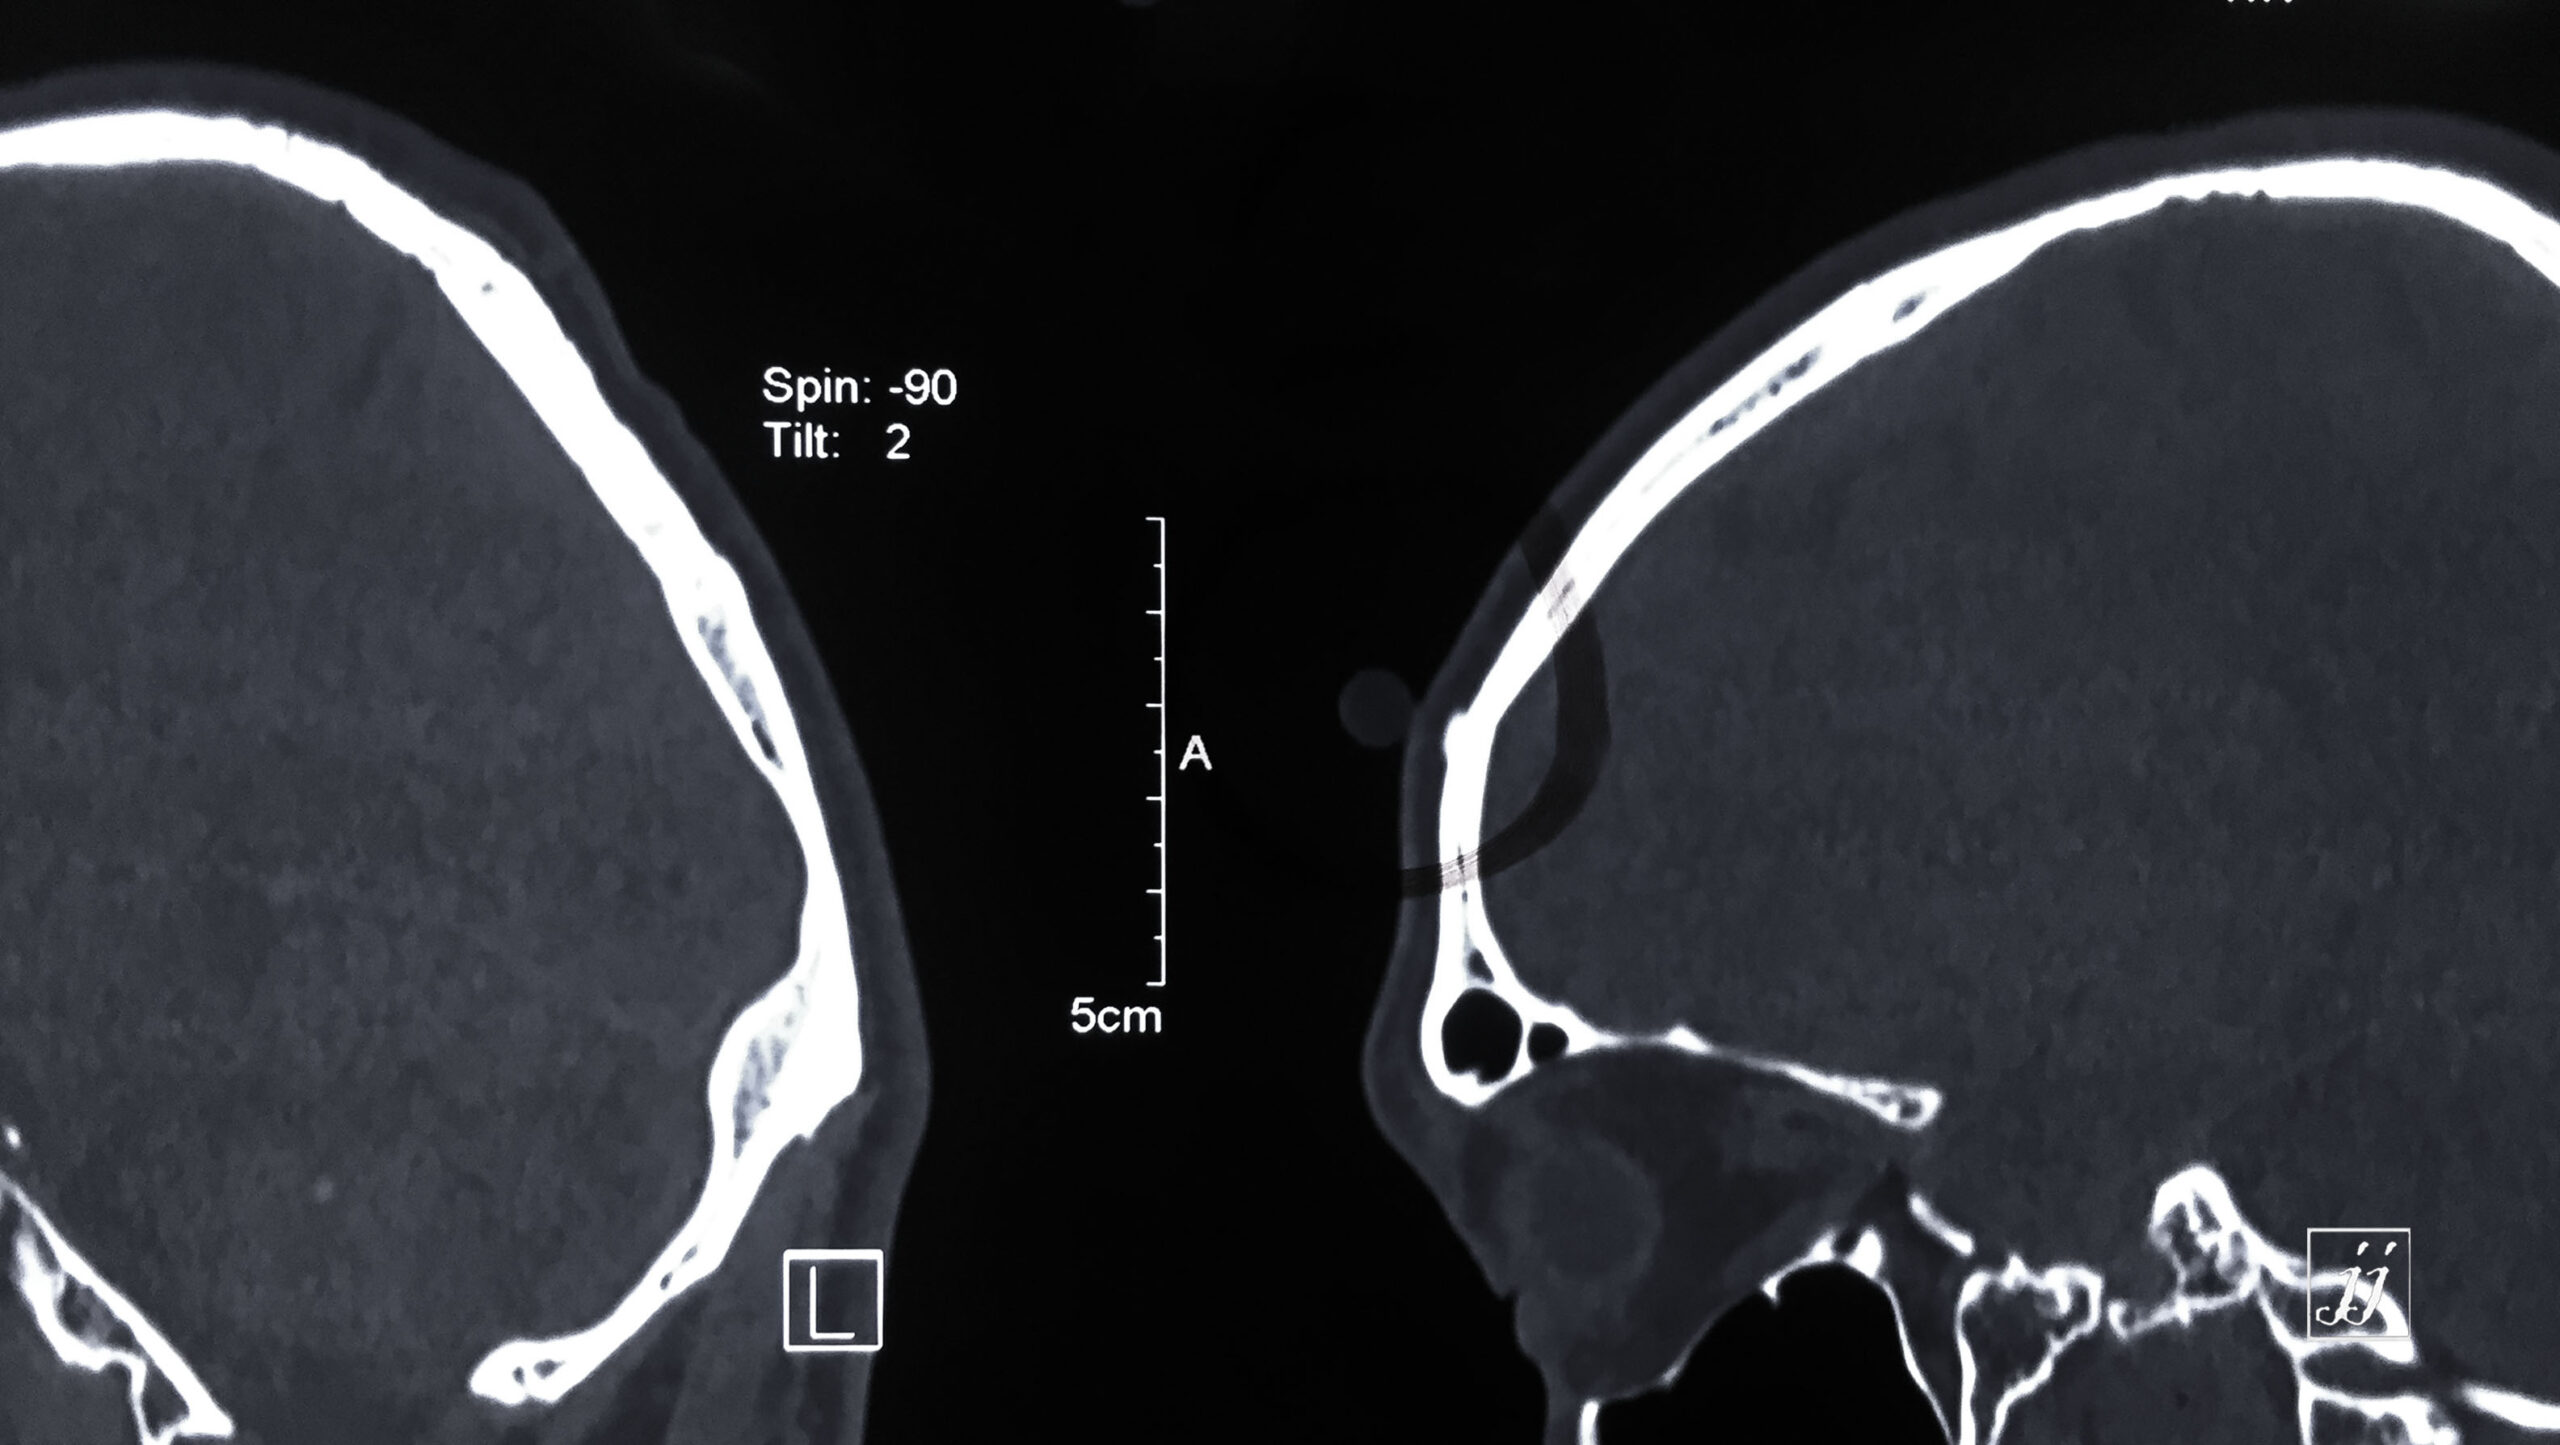

Brain- small osteoma (7)